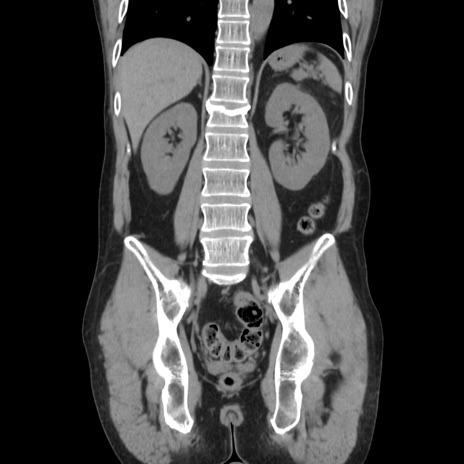

症例37(冠状断像)

【症例】40歳代 男性

【主訴】腹痛

【現病歴】4時間ほど前に電車に乗車中に臍部上より腹痛出現。徐々に増悪し起立困難となり、救急外来受診。生ものは数日食べていない。今朝お雑煮を食べた。

【身体所見】BT 36.8℃、BP 117/84mmHg、HR 91/min、SpO2 97%、苦悶様、腹部:臍上部広範囲圧痛あり、反跳痛±

【データ】WBC 8100、CRP 0.03